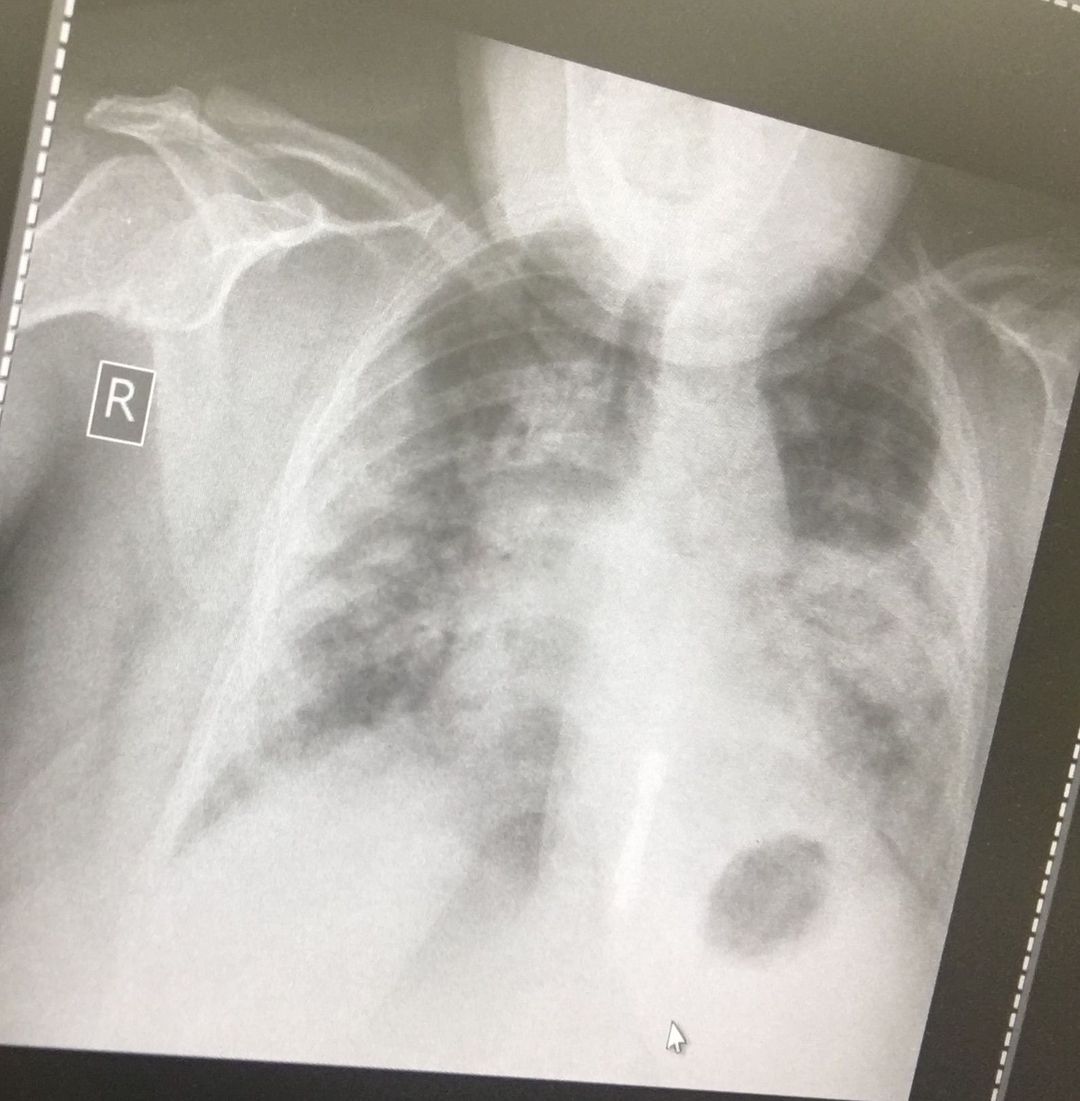

Patient came to emergency room

Cough,severe pain

Bilateral pneumonitis

I think Ca